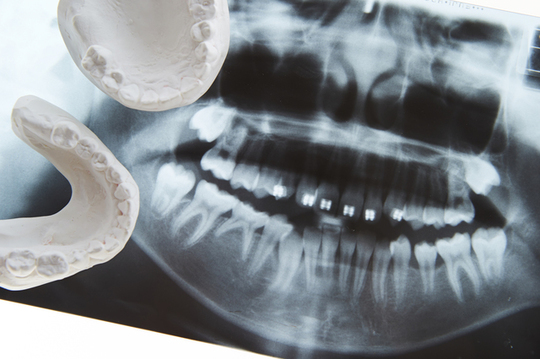

従来のレントゲン撮影では平面的な画像しか得られませんでしたが、歯科用CTではあごの骨の厚みや骨密度を詳細に確認可能。歯や神経の位置なども立体的に把握できるため、精密な診査・診断を行えます。

これまでの歯科用X線写真(パノラマレントゲン)では、お口の中を平面的に撮影していました。歯やあごの骨の大まかな状態確認には問題ありませんでしたが、インプラント治療や親知らずの抜歯など精度が求められる治療では、情報が不足する場合もあったのです。

ところが歯科用CTですと、あごの骨の厚みや高さに加えて、歯の根の先端からあごの骨の中を走る神経・血管までの距離など、より詳細な情報を得られます。

これまでのレントゲン写真(パノラマレントゲン)では得られなかった詳細な情報を、歯科用CTなら立体的に把握できます。360度あらゆる角度から歯やあごの骨の状態を確認することで、インプラントをはじめとする外科治療において、より高い安全性と治療精度の実現が可能になりました。